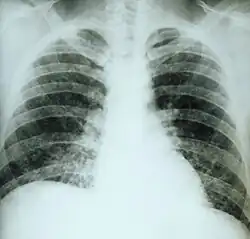

- une primoinfection pulmonaire pseudo-grippale mais avec des images radiologiques marquées : infiltrats, nodules, miliaires. Cette forme bénigne guérit souvent spontanément ;

- une pneumopathie chronique souvent pseudo-tuberculeuse, avec altération de l'état général, qui fait suite à la précédente ;